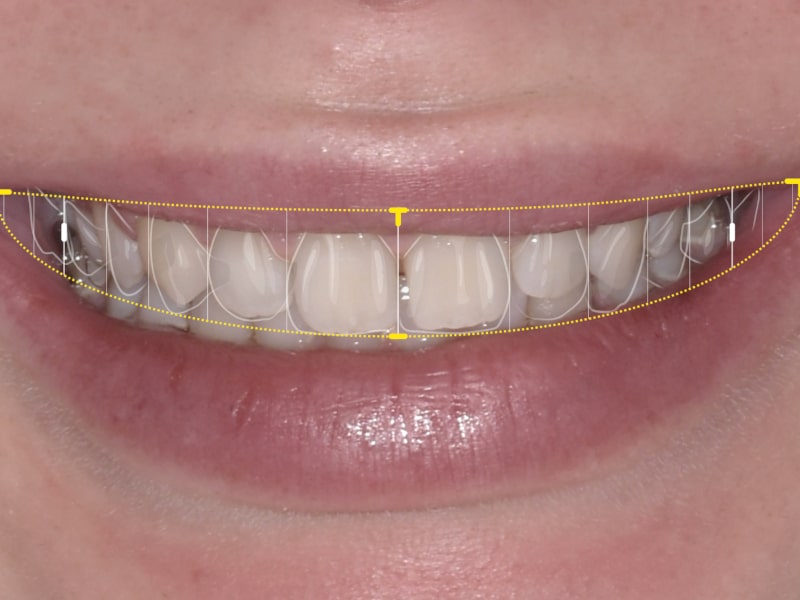

Estetska dentalna medicina

Izbjeljivanje zubi i ljuskice zaštitni su znak Hollywoodskog osmijeha. Izbjeljivanje nije štetno za zube i ne oštećuju caklinu. Marković Dental Clinic uvijek na prvom mjestu ima zdravlje zubi i zadovoljstvo svakog pacijenta.